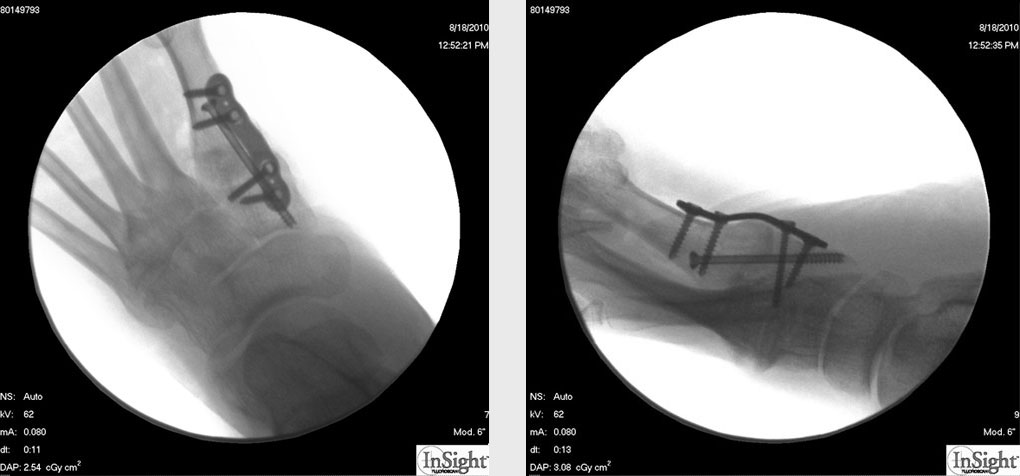

Das hier dargestellte OP-Verfahren beschreibt die Osteosynthese mit einer plantar angebrachten winkelstabilen Platte. Die plantare Platte hat bei der Fusion des TMT1-Gelenks mehrere Vorteile. Dies ist einerseits die optimierte Biomechanik. Bei plantarer Plattenanlage entsteht ein Zuggurtungsmechanismus, der bei Belastung zu einer Kompression der Arthrodese führt. Weiterhin wird die Platte vollständig durch den M. abductor hallucis abgedeckt, was postoperative Wundheilungsstörungen reduziert und in den meisten Fällen eine Metallentfernung überflüssig macht.

Operationstechnik (Fotos)

Zum Lesen der Bildbeschreibung und zur Vollansicht bitte die Bilder anklicken.

Abbildung 2

Abbildung 3

Abbildung 4

Abbildung 5